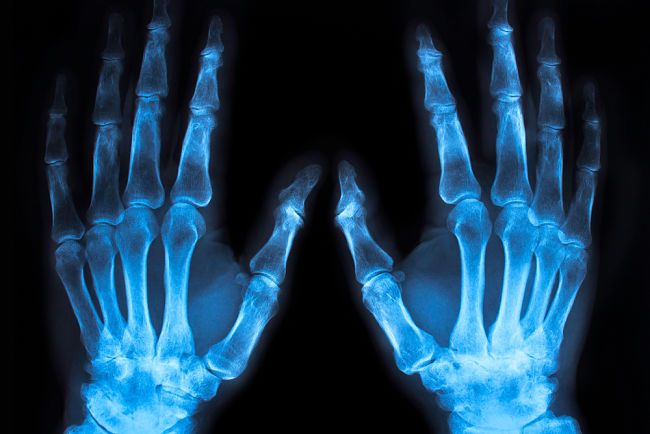

Podobný jev mu nebyl známý z žádné práce jeho kolegů, a tak nové paprsky nazval X a pustil se do jejich zkoumání. Přišel na to, že když krystalky nahradí fotografickou deskou, deska působením záření zčerná. Nový objev ho natolik upoutal, že téměř nevycházel z laboratoře a dokonce v ní i spal. Veřejnosti ho nakonec představil 28. prosince 1895 v předběžném sdělení „O novém druhu paprsků“. Jeho objev zaujal mnoho novin i časopisů a 23. ledna 1896 Röntgen o paprscích X dokonce promluvil na veřejné přednášce, na které nechyběla ani názorná ukázka – nové paprsky byly použity k vyfotografování ruky profesora Alfreda von Koellikera. Nadšený Koelliker pak navrhl, aby se paprsky X nazývaly rentgenovými.